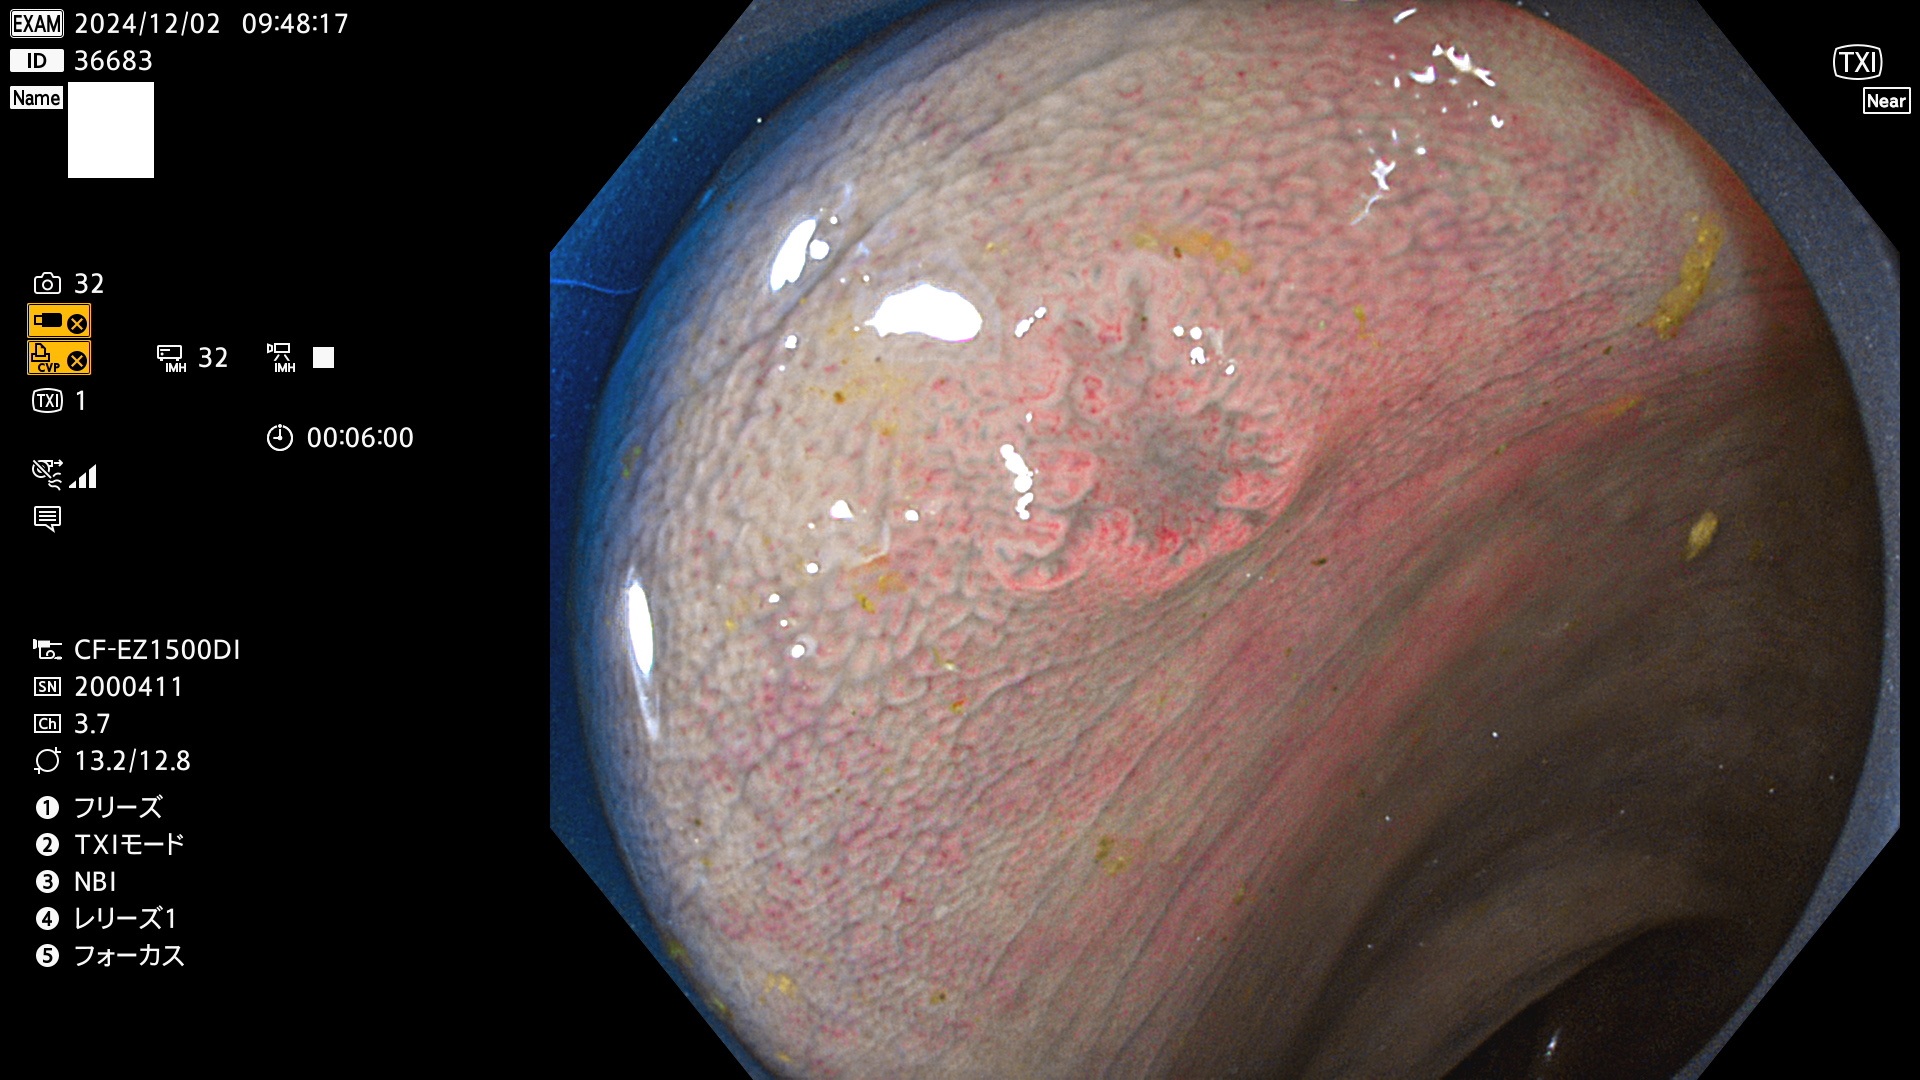

今週のUb、Uc型腺腫

完全に平坦な物をUb、陥凹している物をUcと呼びます。最も発見が難しく危険な病変です。

毎週の検査(木・金・土・日)に発見されたUb、Uc型・腺腫を、その週の日曜の夜にUPし1週間、提示します。

抽出の対象期間 2024年11月28日〜12月2日の5日間(60件の検査)9件 (9/60=15%)